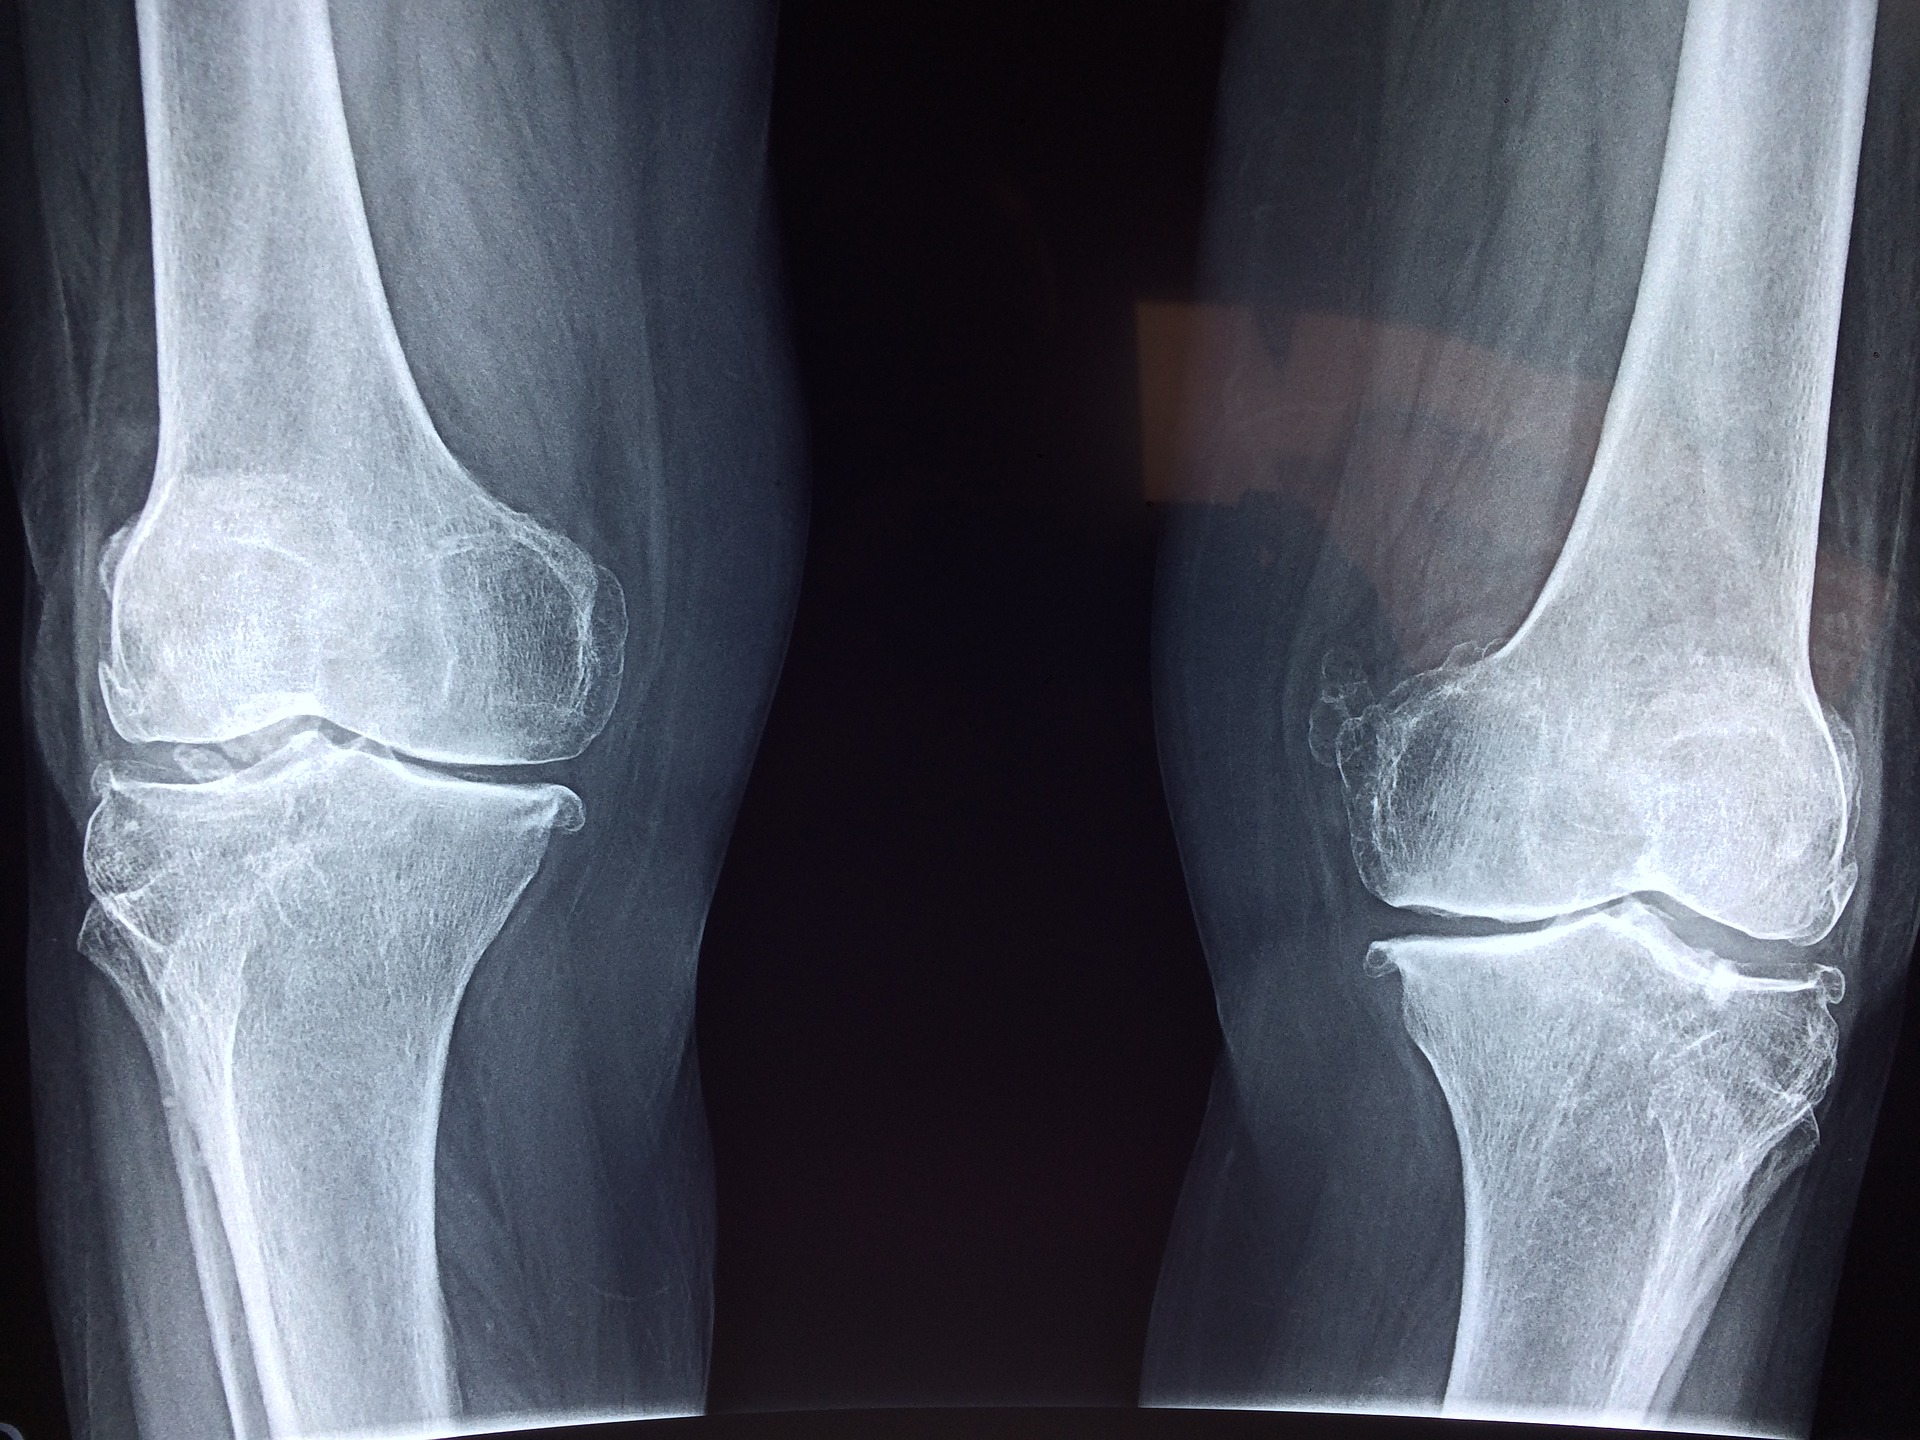

Ogromnym problemem są uszkodzenia ścięgien. Zdarza się to nie tylko sportowcom, ale także osobom aktywnym …